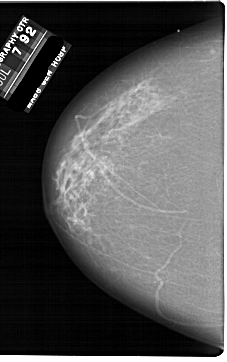

A_1861_1.LEFT_CC

LEFT_CC LINES 6871 PIXELS_PER_LINE 4306 BITS_PER_PIXEL 12 RESOLUTION 43.5 NON_OVERLAY